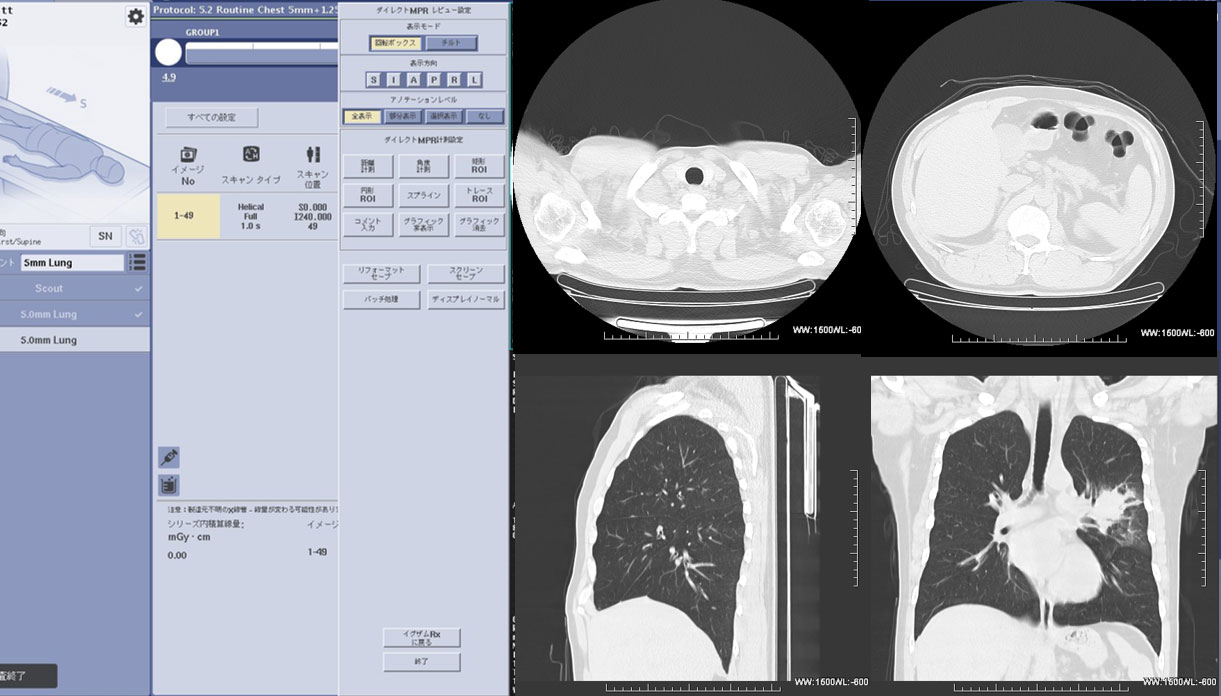

RevolusionACT_Tomiokahc05.jpg

Revolution ACTの操作コンソール画面 -ダイレクトMPR-

撮影と同時にダイレクトMPRが起動し、横断像だけでなく自動で矢状断、冠状断の画像を得ることができます。